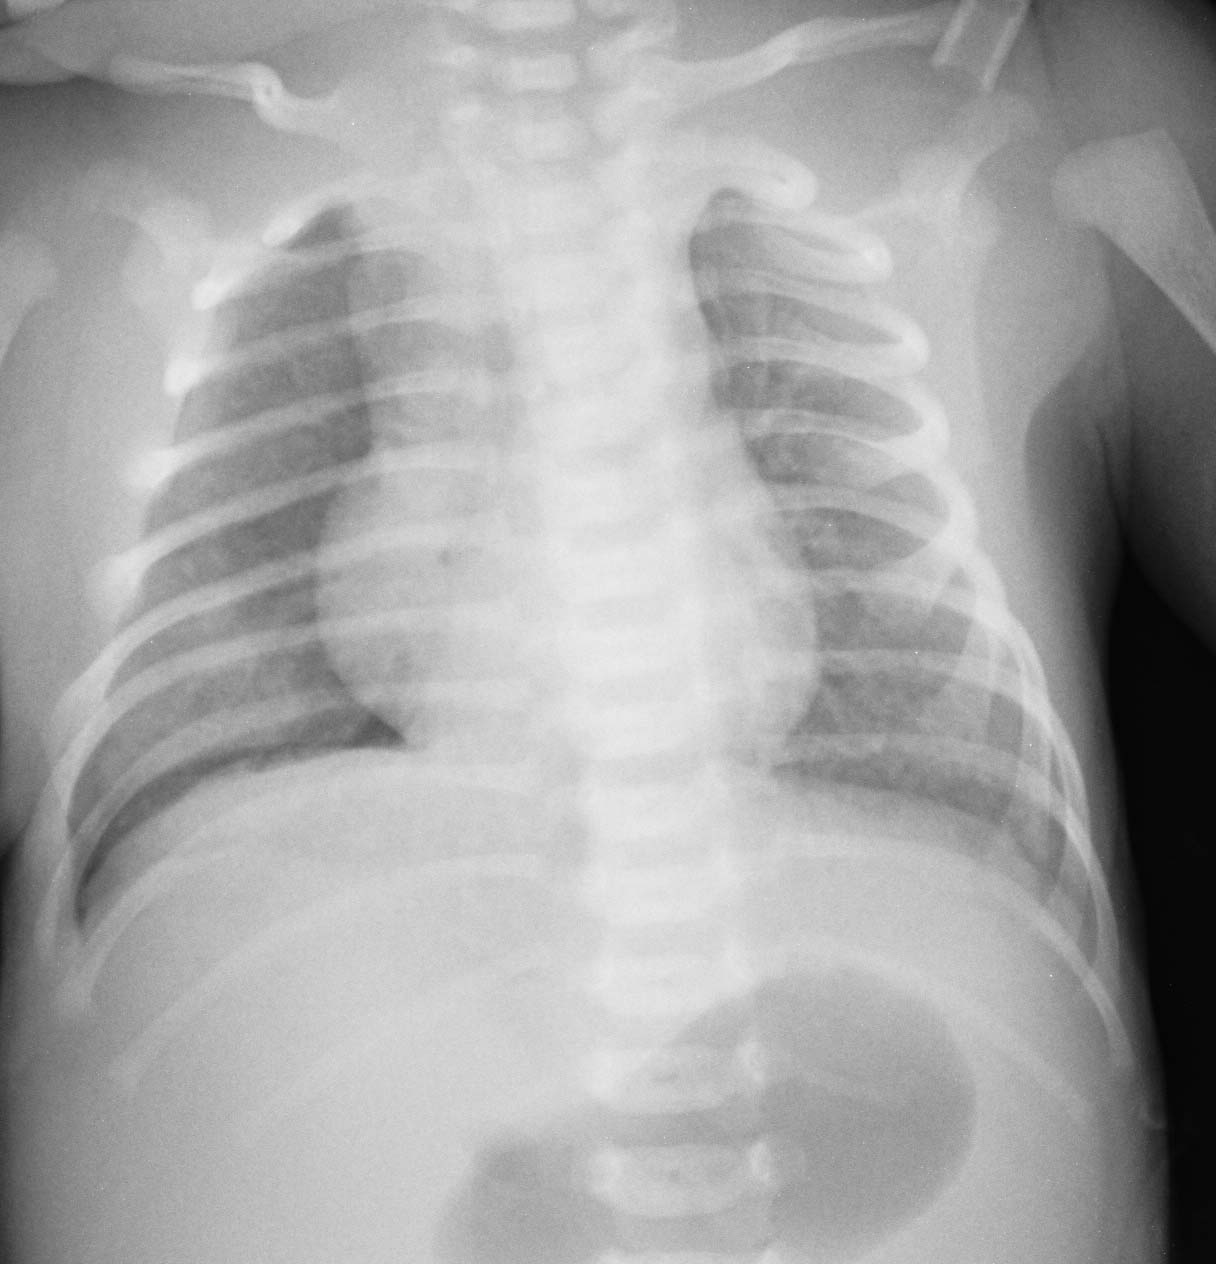

标题: PED0742:请高手帮我看看这是不是气胸,病理基础是什么?

患者,男婴,生后7小时,全身发绀,呼吸急促。

未处理第2天

肺透明膜病伴气胸

不是气胸,由于是仰卧位摄片,背部的皮肤皱褶造成的假象,这种情况在成人也可出现,若不注意,很容易误为气胸.若平时注意观察,这种例子时有见到.

是皮肤邹折造成的假像。